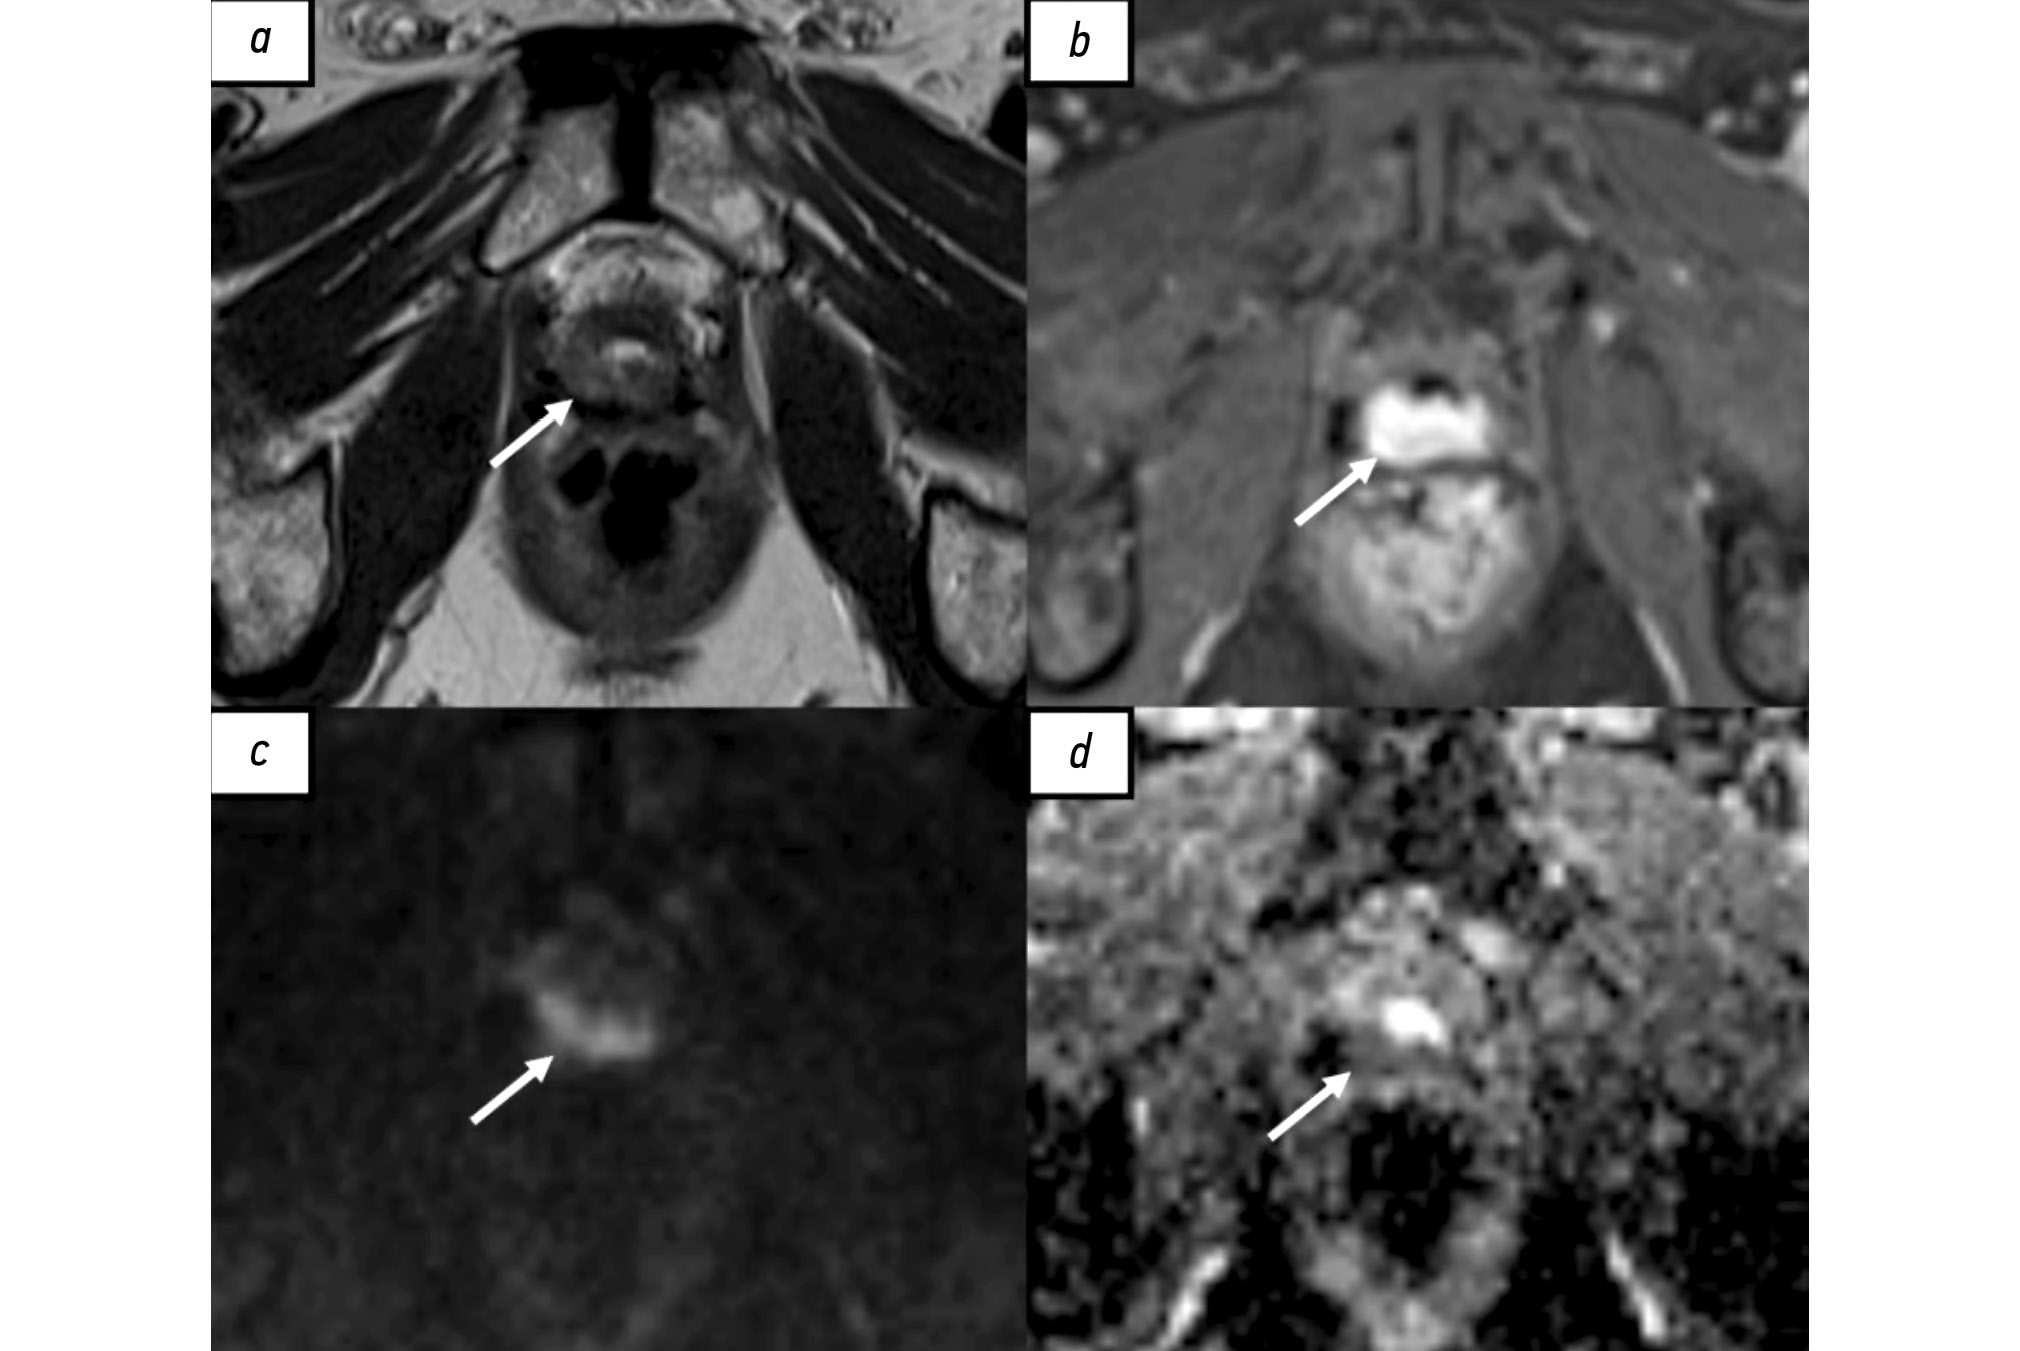

МРТ наиболее широко применяют в диагностике местного рецидива РПЖ. Общепринятой специализированной шкалы оценки наличия локального рецидива, по аналогии со шкалой PI-RADS (Prostate imaging reporting and data system), до настоящего времени не создано. В большинстве исследованиях используют протокол сканирования, аналогичный мультипараметрической МРТ (мпМРТ), применяемый для первичной диагностики РПЖ [35]. Радикальная простатэктомия подразумевает тотальное удаление предстательной железы, семенных пузырьков и, в ряде случаев, тазовую лимфодиссекцию. При проведении МРТ пациентам после радикального хирургического лечения предстательную железу и семенные пузырьки не визуализируют, однако определяют везикоуретральный анастомоз между низведённым мочевым пузырём и экстрапростатической частью уретры. В его зоне в норме определяют фиброзную ткань, гипоинтенсивную на всех импульсных последовательностях, не имеющую признаков рестрикции диффузии и раннего накопления контрастного вещества. У некоторых пациентов визуализируют резидуальные семенные пузырьки, расположенные в типичных местах, с наличием или отсутствием фиброзных изменений [36]. Характерный участок локального рецидива имеет вид мягкотканного образования с промежуточной интенсивностью сигнала на Т2-взвешенных изображениях (ВИ), с признаками рестрикции диффузии и раннего накопления контрастного вещества (рис. 1). Таким образом, сигнальные характеристики локального рецидива РПЖ схожи с аналогичными характеристиками первичной опухоли [37]. Интерпретация диффузионно-взвешенных изображений иногда затруднена в связи с наличием артефактов от шовного материала. Сочетанный анализ Т2-ВИ, динамических постконтрастных и диффузионно-взвешенных изображений позволяет с большей уверенностью отличить местный рецидив от воспалительных изменений и резидуальной ткани предстательной железы, а также фиброзной и грануляционной [38].

Рис. 1. Рецидив рака предстательной железы в области везикоуретрального анастомоза у пациента после радикальной простатэктомии по результатам магнитно-резонансной томографии, собственное наблюдение: a — Т2-взвешенное изображение в аксиальной плоскости. Зона промежуточной интенсивности магнитно-резонансного сигнала в области везикоуретрального анастомоза по задней поверхности (стрелка); b — Т1-взвешенное изображение с жироподавлением в аксиальной плоскости. Зона накопления контрастного вещества в области везикоуретрального анастомоза по задней поверхности (стрелка). c — диффузионно-взвешенное изображение в аксиальной плоскости, d — карта измеряемого коэффициента диффузии. Зона рестрикции диффузии в области везикоуретрального анастомоза по задней поверхности (стрелки).